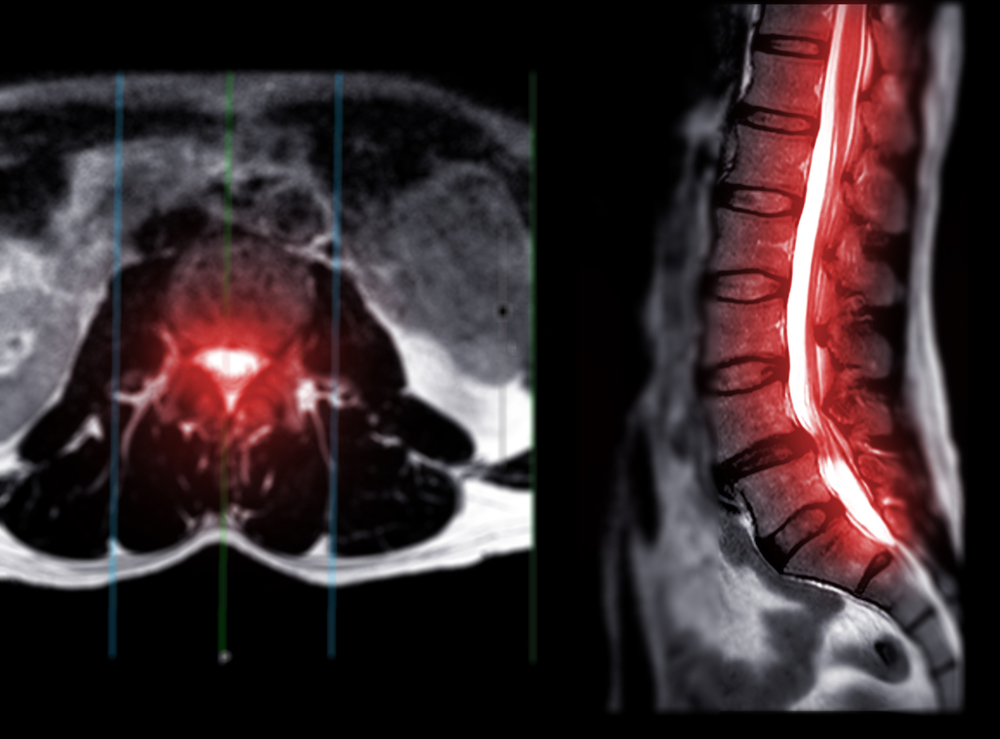

آزمایشهای تصویربرداری: تکنیکهایی مانند اشعه ایکس (X-rays)، امآرآی (MRI) یا سیتیاسکن (CT scans) برای مشاهده ستون فقرات و شناسایی نواحی باریکشده.